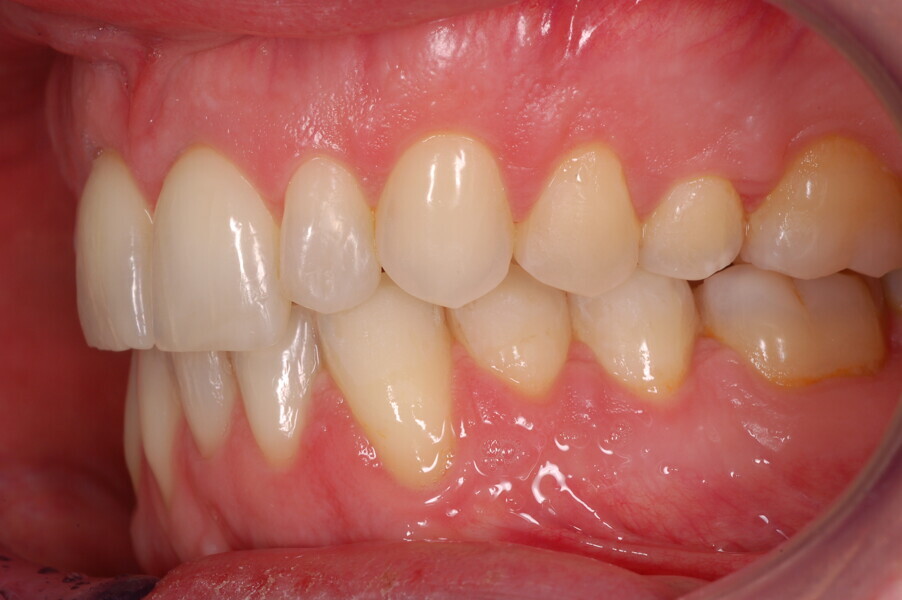

A healthy 39-year-old man presented to our orthodontic office with the chief complaint of an unattractive dental appearance and fear of the orthognathic surgery proposed by another orthodontist. Clinically, the patient’s profile was straight, and the frontal view did not show any facial asymmetry. The functional examination did not reveal any mandibular deviation or reduced movements. The patient had no joint pain, and no joint noise was observed.

Figs. 1–8: Pretreatment facial and intra-oral photographs.

From the periodontal point of view, the patient showed a good attitude to oral hygiene, but crowding of the mandibular incisors made cleaning difficult in that area, causing plaque accumulation and localised gingival inflammation. The panoramic radiograph revealed the presence of the mandibular third molars and confirmed the absence of the mandibular right central incisor (Fig. 10).

The cephalometric analysis showed a skeletal Class II malocclusion (convexity of Point A: 4.9 mm), a slightly retruded chin position (facial depth: 78.1°) and a skeletal open bite tendency (lower facial height: 53.19°; facial axis: 80.58°; Fig. 9). The mandibular incisors were lingually tipped (Li–APog: 9.3°) and retruded (Li–APog: 1.55 mm), and there was an increased inter-incisal angle of 142.9°.